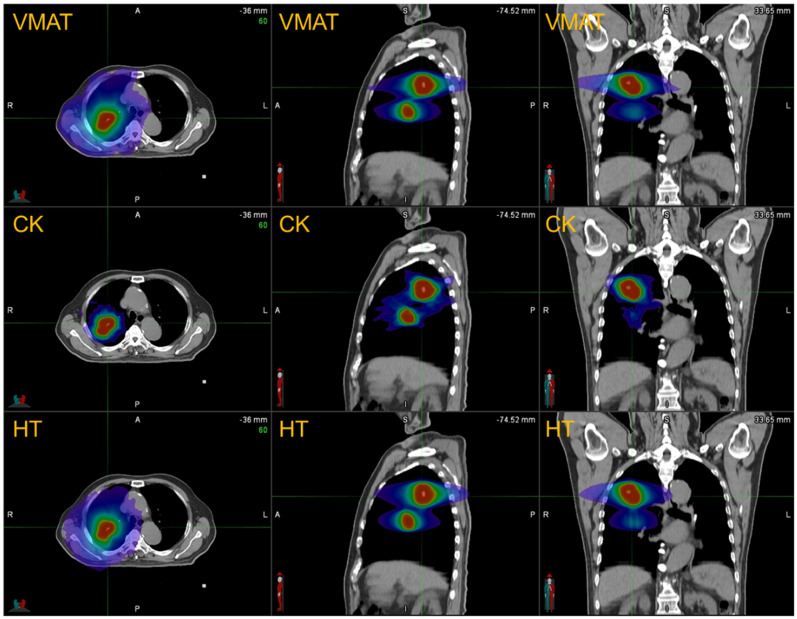

目的比较体积调节弧线治疗(VMAT)、螺旋断层治疗(HT)和射波刀(CK)治疗肺少转移瘤的剂量学和生物学风险。方法和材料本回顾性研究纳入了21例肺少转移患者,每个患者有2或3个病灶,之前接受过立体定向全身放射治疗(SBRT)。为每位患者制定VMAT、HT和CK计划。评估了计划靶体积(PTV)和危及器官(OARs)的剂量分布。评估了放射性肺炎(RP)、冠状动脉疾病(CAD)和充血性心力衰竭(CHF)三种生物学风险。同时记录监测单位(MUs)和光束接通时间。结果所有技术均能产生临床可交付的方案。VMAT计划、CK计划和HT计划的预期生物风险RP为6.69%、5.05%、5.88%,CAD为1.20%、1.15%、1.17%,CHF为1.26%、1.19%、1.22%。与VMAT和HT计划相比,CK计划RP的预期风险略低(p

PurposeTo compare the dosimetry and biological risk of volumetric modulated arc therapy (VMAT), helical tomotherapy (HT) and cyberKnife (CK) in the treatment of lung oligometastases.Methods and materialsThis retrospective study included a cohort of 21 lung oligometastasis patients, each with 2 or 3 lesions, who had previously undergone stereotactic body radiation therapy (SBRT). VMAT, HT and CK plans were made for each patient. The dose distribution of planning target volume (PTV) and organs at risk (OARs) were evaluated. Three biological risks were evaluated, namely radiation pneumonitis (RP), coronary artery disease (CAD) and congestive heart failure (CHF). Monitor Units (MUs) and beam-on-time were also recorded.ResultsAll techniques were able to produce clinically deliverable plans. The expected biological risks for VMAT plans, CK plans, and HT plans were 6.69%, 5.05%, 5.88% for RP, 1.20%, 1.15%, and 1.17% for CAD, 1.26%, 1.19%, and 1.22% for CHF. The expected risks of RP were slightly lower in CK plans compared to VMAT and HT plans (p < 0.001), with VMAT plans showing the highest expected risks. For central lung cancer, the expected CAD risks of CK and HT plans were lower than those of VMAT plans (p < 0.05). The delivery efficiency of VMAT plans was significantly higher than that of CK plans and HT plans.ConclusionsAll three techniques, VMAT, HT, and CK, meet the therapeutic requirements for target coverage and dose constraints for OARs. Although there are statistical differences, the difference between the expected risk values of RP and CAD is very small, so the clinical manifestations may not show differences.